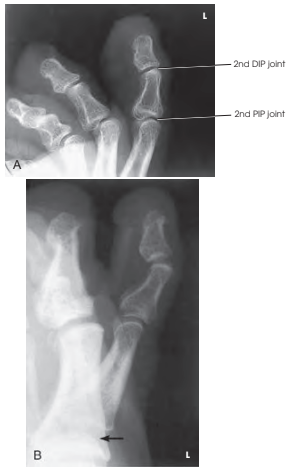

Structures shown (촬영 구조)

- 해당 발가락의 지골(Phalanges)과 IP 관절이 명확히 보이는 측면 투사 이미지를 제공합니다.

- 중첩된 발가락이 있을 경우, 근위 지골(proximal phalanx)은 보여야 합니다.

Evaluation Criteria (평가 기준)

- 전체 발가락이 포함되어야 하며, 인접한 발가락의 중첩이 없어야 합니다.

- 피할 수 없을 경우 근위 지골(proximal phalanx)이 보여야 합니다.

- 발가락이 정측면 위치에 있어야 합니다.

- 정상적인 경우, 발톱(toenail)이 옆모습으로 보이며, 평평한 발바닥 표면이 확인됩니다.

- 발가락의 회전이 없어야 합니다.

- 열려 있는 IP 관절 공간과 경우에 따라 열려 있는 MTP 관절 공간도 포함됩니다.

- 연부 조직과 뼈의 세부 구조가 명확하게 나타나야 합니다.